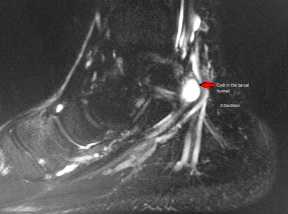

Рис 1. Анатомические особенности канала предплюсны.

Удерживатель сгибателей представляет собой связку, которая, в норме, ограничивает канал предплюсны, а также удерживает находящиеся в нем анатомические элементы. Однако, при этом, именно связка может спровоцировать различного рода нарушения анатомической структуры голеностопа и стопы путем патологического сжимания содержимого канала.

Итогом такого сжимания становится регулярное чрезмерное растяжение расположенного в нем нерва, переходящего, со временем, в СТК.